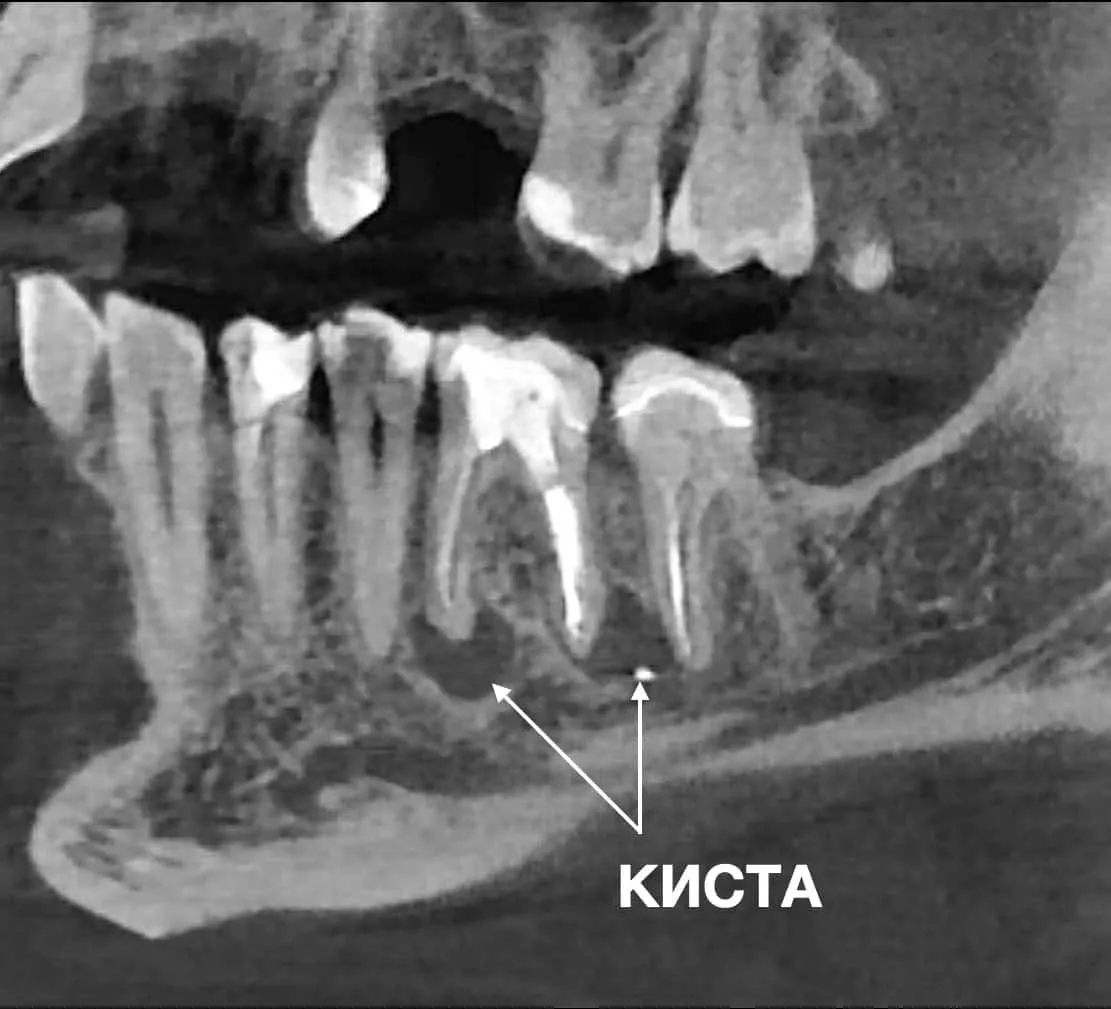

ПРИМЕР УСПЕШНОГО УДАЛЕНИЯ КИСТЫ ЗУБА В СТОМАТОЛОГИЧЕСКОМ ЦЕНТРЕ OLANKO DENTAL STUDIO

Часто апикальная хирургия является единственным способом избежать удаления зуба.

Также показаниями есть истинные кисты и инфекция вне корневого канала, на которые мы не можем повлиять консервативным эндодонтическим лечением.